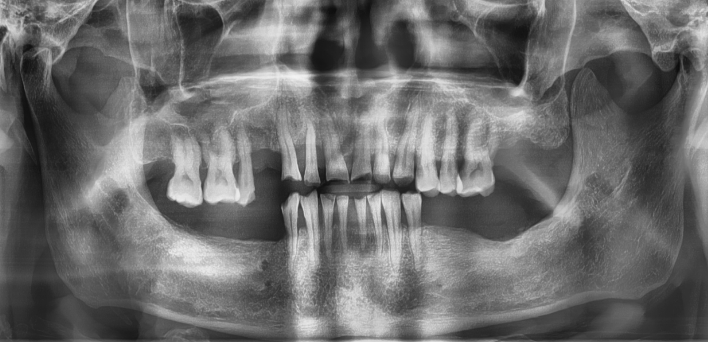

Before Before

2020.02.30

환자 특징01무치악 상태

환자 특징02수년간 무치악으로 지내심

임플란트가 불가능할것이라

생각하고 내원

위, 아래 6개씩 식립

디지털 풀아치 임플란트